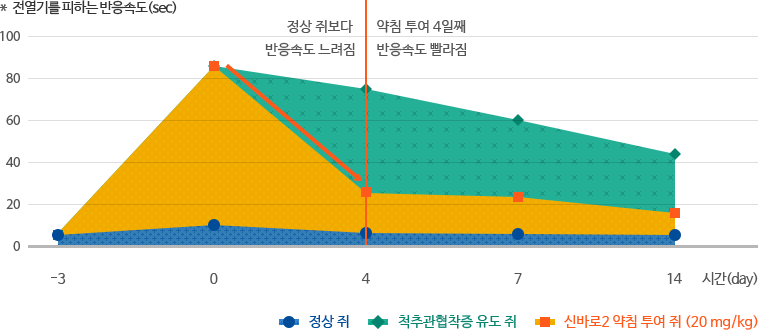

감각능력 회복

척추관협착증을 유도한 쥐는 전열기 테스트에서 온도에 대한 인식과 반응이 느려져 전열기를 피하는 속도가 눈에 띄게 느려졌습니다.

신바로2를 투여한 그룹은 감각능력이 회복되어 4일째부터 전열기를 피하는 속도가 눈에 띄게 빨라졌습니다.